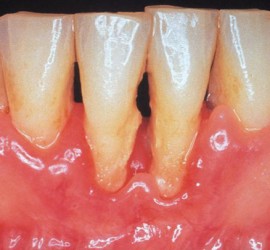

Лечение пульпита. При лечении пульпита перед врачом встают следующие задачи: избавление больного от болевых ощущений, ликвидация инфекционно-токсического очага в пульпе зуба, восстановление формы и функции зуба. Первую помощь больному острым пульпитом может оказать средний медработник или врач любого другого профиля. Она заключается в назначении внутрь обезболивающих препаратов типа анальгина, амидопирина, […]